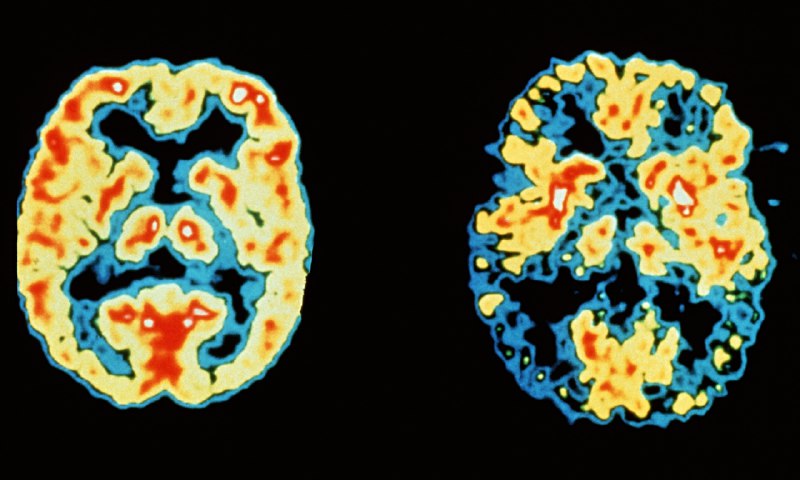

یافتههای یک پژوهش جدید نشان میدهد سلولهای بدن مانند مغز، ژن حافظه دارند

تصور علمی ما از حافظه در آستانه تحولی بنیادین قرار گرفته است. بر اساس پژوهشهای نوین، توانایی ذخیره و پردازش خاطرات، برخلاف باور پیشین، تنها به نورونهای مغزی محدود نمیشود و سلولهای دیگر بدن نیز از این توانایی برخوردارند.

به گزارش نوروساینس نیوز، مطالعهای که پژوهشگران دانشگاه نیویورک انجام دادند، نشان میدهد ویژگی منحصر به فرد نورونهای مغزی در فعالسازی «ژن حافظه» در پاسخ به محرکهای شیمیایی، تنها محدود به مغز نیست و سلولهای دیگر بدن نیز این توانایی را دارند.

اهمیت این یافته را میتوان از دو جنبه بررسی کرد؛ از یک سو، این پژوهش خاطرنشان میکند که یادگیری از طریق تکرار میتواند ویژگی ذاتی تمام سلولهای بدن باشد و از سوی دیگر، این مطالعه جدید میتواند مسیرهای نوینی را در درمان اختلالات حافظه و یادگیری بگشاید.

نیکولای کوکوشکین، پژوهشگر ارشد این تحقیق، که نتایج آن در مجله «نیچر کامیونیکیشنز» منتشر شد، گفت: «اگرچه همواره یادگیری و حافظه را منحصر به مغز و سلولهای مغزی میدانستیم، پژوهش ما نشان میدهد که سلولهای دیگر بدن نیز میتوانند یاد بگیرند و خاطرات را شکل دهند.»

بررسی اثر تکرار فاصلهدار در سلولهای غیرعصبی انسان:

هدف این پژوهش، درک بهتر رفتار سلولهای غیرمغزی در فرآیند حافظه بود. بهطور خاص، محققان به دنبال بررسی این موضوع بودند که آیا این سلولها نیز از یک ویژگی شناختهشده عصبی به نام «اثر تکرار فاصلهدار» بهره میبرند یا خیر.

«اثر تکرار فاصلهدار» یکی از ویژگیهای کلیدی در شکلگیری حافظه است. این اثر بیانگر این واقعیت است که انسانها در یادگیری مطالب با فواصل زمانی مشخص، عملکرد بهتری نسبت به یادگیری فشرده دارند.

به عبارت دیگر، مطالعه با فاصلههای زمانی منظم، نسبت به روش فشرده (که بهطور معمول برای آمادگی در آزمونها مورد استفاده قرار میگیرد)، اثربخشی بیشتری در حفظ اطلاعات دارد.

بررسی رفتار سلولهای غیرمغزی در فرآیند یادگیری:

محققان در این پژوهش به مطالعه دو نوع سلول غیرمغزی انسانی در محیط آزمایشگاه پرداختند. آنها سلولهایی از بافت عصبی و کلیه را انتخاب کردند و در شرایطی مشابه سلولهای مغزی قرار دادند.

در این آزمایش، سلولها در معرض الگوهای متنوعی از سیگنالهای شیمیایی قرار گرفتند، درست مانند فرآیندی که هنگام یادگیری اطلاعات جدید در مغز رخ میدهد و نورونها با انتقالدهندههای عصبی تعامل میکنند.

محققان این فرآیند را در طول زمان تکرار کردند تا چگونگی یادگیری این سلولها را بررسی کنند.

واکنش شگفتانگیز سلولهای غیرمغزی در فرآیند حافظه:

آزمایشها نشان داد که سلولهای غیرمغزی، درست مانند نورونهای مغز، توانایی فعالسازی «ژن حافظه» را دارند.

این همان ژنی است که در مغز، هنگام شناسایی الگوهای اطلاعاتی و بازسازی اتصالات عصبی برای شکلگیری خاطرات فعال میشود.

برای پایش فرآیند حافظه و یادگیری، دانشمندان با مهندسی ژنتیک، سلولهای غیرمغزی را طوری تغییر دادند که پروتئینی درخشان تولید کنند. این پروتئین نشان میداد که ژن حافظه چه زمانی فعال و چه زمانی غیرفعال میشود.

کشف الگوی یادگیری در سلولهای غیرمغزی:

یافتههای پژوهش حاکی از آن است که این سلولها توانایی تشخیص الگوی تکرار پالسهای شیمیایی را دارند.

این پالسها که از روی انتقالدهندههای عصبی در مغز شبیهسازی شده بودند، به جای یک محرک طولانی و پیوسته، بهصورت متناوب ارائه میشدند، درست مانند نورونهای مغز ما که در فرآیند یادگیری به جای دریافت حجم زیادی از اطلاعات در یک جلسه، آن را در فواصل زمانی دریافت میکنند.

همچنین مشخص شد زمانی که این پالسها با فاصلههای زمانی منظم ارسال میشدند، «ژن حافظه» قویتر و طولانیتر فعال میماند، در مقایسه با حالتی که همان میزان محرک به صورت یکجا ارائه میشد.